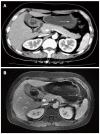

Gastritis cystica profunda is a relatively rare disease, usually observed at anastomotic sites in stomachs of patients that have undergone gastric procedures. We present the rare case of an elevated lesion in the anterior wall of the gastric antrum of a 43-year-old Chinese woman who had never undergone gastric surgery and had no gastrointestinal tract symptoms. Although the physical examination and laboratory data showed no abnormalities, endoscopic ultrasonography revealed an anechoic cystic structure. Abdominal computed tomography and magnetic resonance imaging showed the gastric wall of the greater curvature of the antrum was markedly and irregularly thickened, and mild to moderate enhancement was observed around the lesion with no enhancement in the central portion, suggestive of a gastrointestinal stromal tumor. The patient underwent a distal gastric resection of the 2.5 cm × 1.5 cm lesion. A postoperative pathologic examination showed dilated cystic glands in the muscularis mucosa and submucosal layers and erosion of the mucosal surface of the tumor, confirming the diagnosis of gastritis cystica profunda without malignancy.